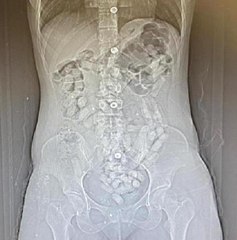

İran'dan gelen 5 kişinin midesinde 6 kilo 145 gram afyon sakızı ele geçirildi Yanlarında tokluk hissi veren ve mide-bağırsak temizleyici ilaçların olmasıyla yakayı ele verdilerERZURUM Erzurum'da polis ekipleri tarafından İran'dan gelen yolcu otobüsünde ve bir araçta yapılan aramalarda... brİran'dan gelen 5 kişinin midesinde 6 kilo 145 gram afyon sakızı ele geçirildibr Yanlarında tokluk hissi veren ve mide-bağırsak temizleyici ilaçların olmasıyla yakayı ele verdilerbrERZURUM Erzurum'da polis ekipleri tarafından İran'dan gelen yolcu otobüsünde ve bir araçta yapılan aramalarda şüpheli hareketlerde bulunan 5 kişi gözaltına alındı. Kontrol amaçlı hastaneye götürülen 5 kişinin yapılan incelemede toplamda 6 kilo 145 gram afyon sakızı ve 709,83 gram eroin yuttukları tespit edildi.